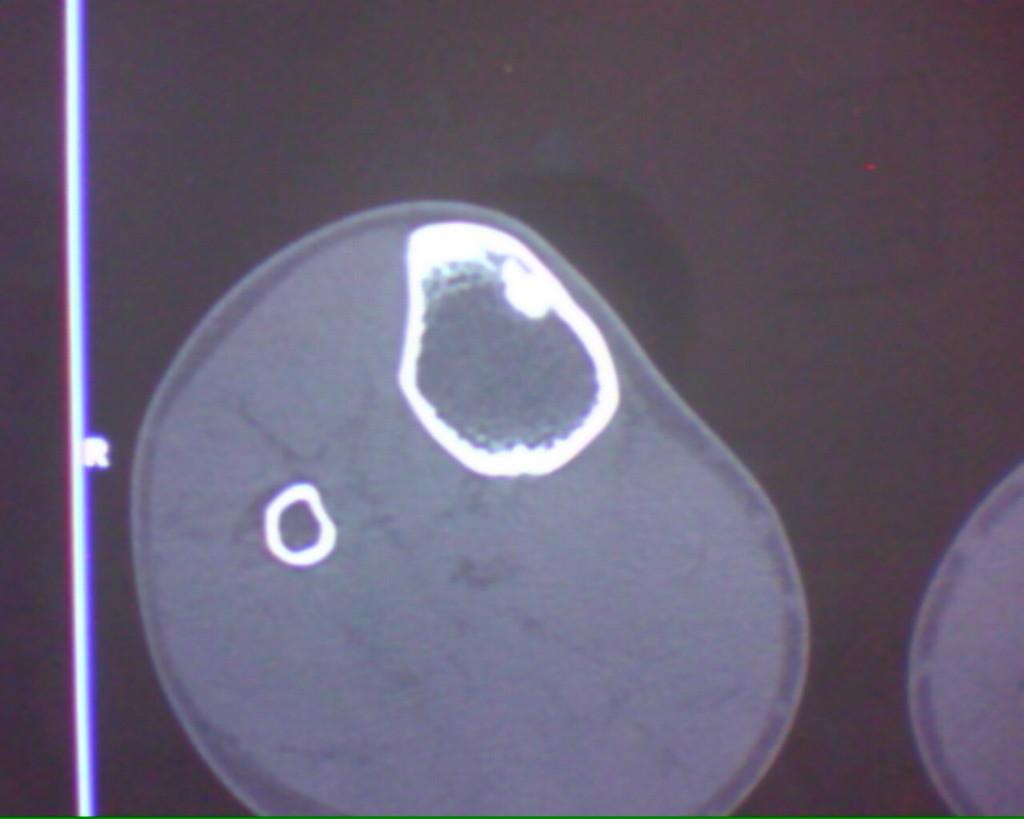

标题: CT19926:右胫骨上段高密度病变

男性,47岁,在一次外伤摄片中发现右胫骨上段条状高密度影,ct横断面上发现条状高密度影(钙化及骨化密度)位于胫骨皮质下,和皮质紧密相连,我考虑纤维性骨皮质缺损钙化可能性大,大家认为呢?大家注意看定位片,高密度病灶是很长的,横断面我只是选取了其中的几个层面。

这是一例经病理证实的纤维性骨皮质缺损钙化病例。

大家注意看定位片,高密度病灶是很长的,横断面我只是选取了其中的几个层面。